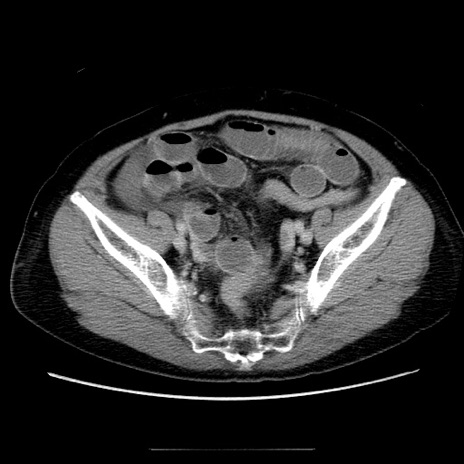

症例5(横断像)

冠状断像

【症例】70歳代女性

【主訴】お腹が張る

【現病歴】1週間くらい前から腹部膨満の自覚あり。昨日夜から増悪したため、本日救急外来受診。

【身体所見】意識清明、BT 36.5℃、BP 165/106mmHg、HR 80bpm、SpO2 98%、腹部:膨満、軟、自発痛・圧痛なし、触診にて不快感あり、腸蠕動音:減弱

【データ】WBC 12600、CRP 1.04